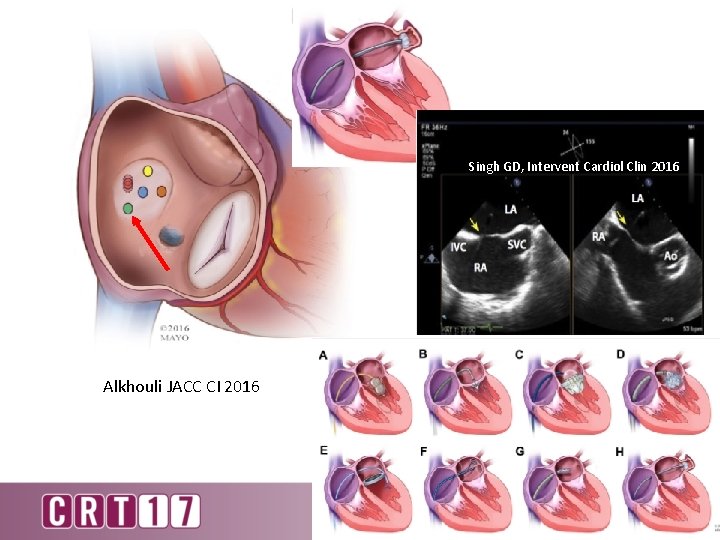

Singh GD, Intervent Cardiol Clin 2016 Alkhouli JACC CI 2016